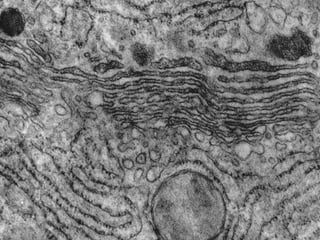

Este documento presenta imágenes microscópicas de diferentes tipos de tejidos y estructuras celulares teñidas con varios métodos histológicos. Incluye fotografías que muestran fibras de colágeno, elásticas y reticulares en diversos órganos, así como membranas basales y células especializadas de órganos como riñones, glándulas mamarias y próstata. El propósito es demostrar la aplicación de técnicas histológicas para visualizar componentes celulares y tej